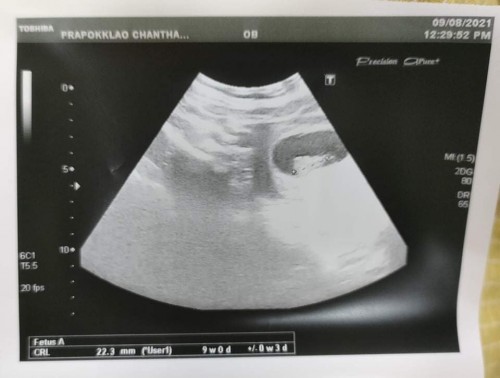

อยากสอบถามแม่ๆ คะ วันนี้หนูไปหาหมอ อายุครรภ์วันนี้ได้11 สัปดาห์ กับ1วัน แต่พอซาวในใบซาวมันได้แค่ 9 สัปดาห์ หนูไม่เข้าใจ หนูถามหมอ เค้าบอกให้นับตามใบซาวน์ แต่คนซาวท้องให้หนู เหมือนพึ่งจบหมอเลย หนูพยายามถามเค้าให้เข้าใจ เค้าก็บอกให้ดูตามใบซาวน์ ถ้าใบซาวน์9สัปดาห์ ในครรภ์ก็คือ9สัปดาห์ แล้วแบบนี้หนูจะนับอายุครรภ์ยังไงคะ #ท้องแรกคะ #ขอบคุณสำหรักคำตอบค่ะ